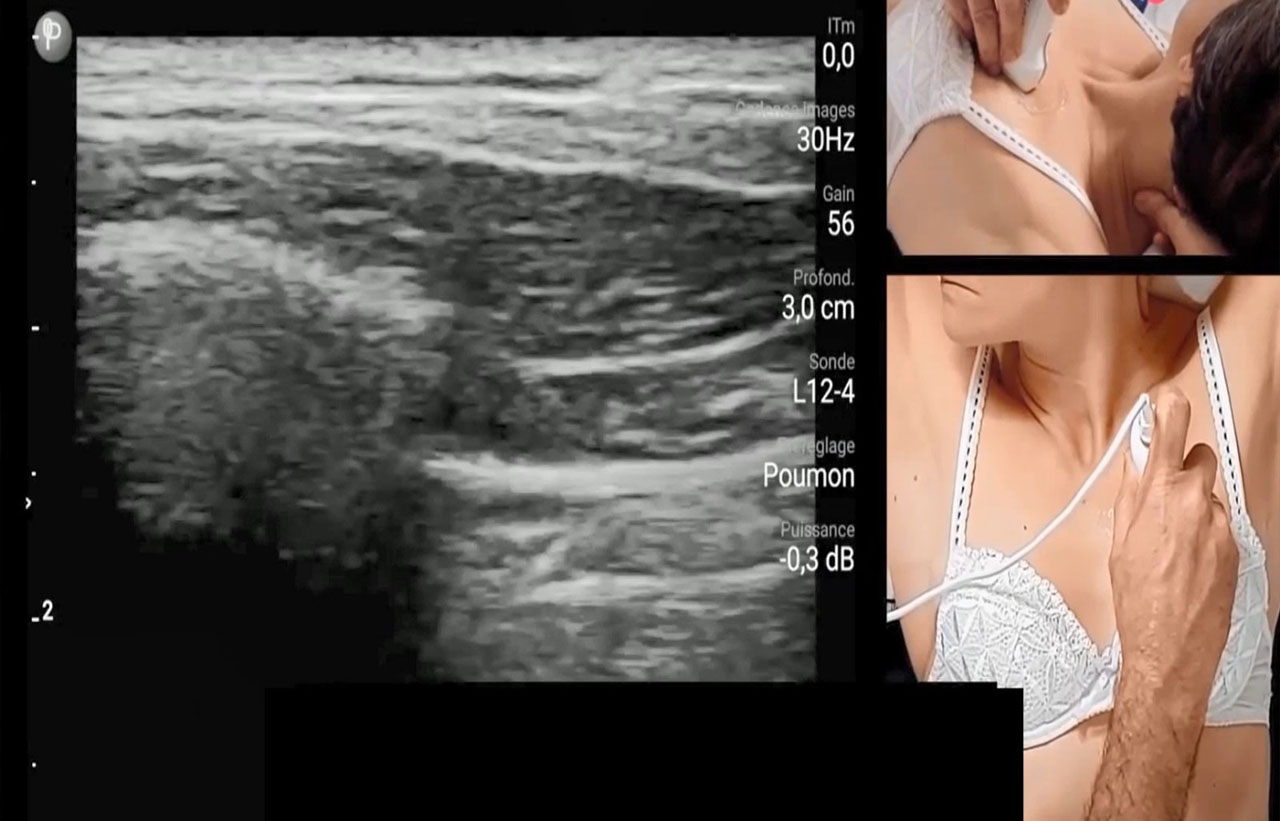

- Detection of patients with COVID with respiratory distress by simple examinations,

- Sorting patients after their arrival by gravity with screening methods,